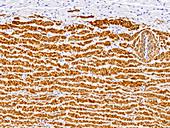

13613434 - Muscular artery and nerves, light micrograph